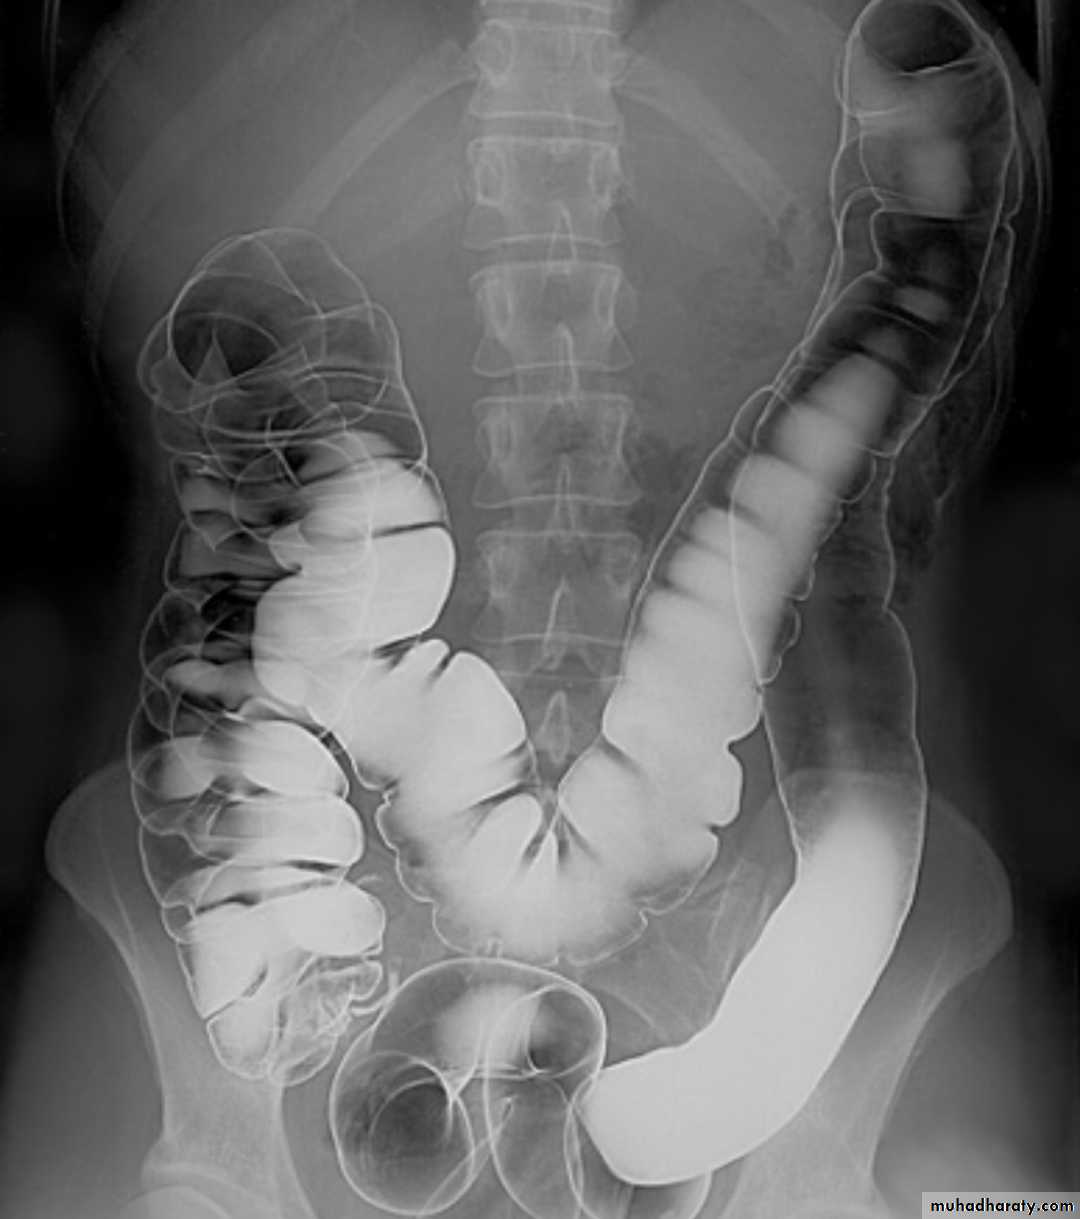

Ba –enema examination

A barium enema is an x-ray examination of the colon and rectum that helps a doctor identify inflammation, polyps, or cancer.Before a barium enema, you will need to empty your colon by following a restricted diet and using a laxative or enema.

During the examination, a liquid called barium is delivered into the colon through the anus and x-rays are taken.

Colonic diverticulosis

refers to the presence of multiple diverticula. It is quite distinct from diverticulitis which describes inflammation and infection of one or multiple diverticula.Radiographic features

Diverticula range in size from a few millimeters to a few centimetersBarium enema

Both single and double contrast barium enemas are able to demonstrate diverticula as barium-filled out-pouchings.